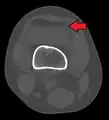

Tibial plateau fracture

Other namesFractures of the tibial plateau

A severe tibial plateau fracture with an associated fibular head fracture